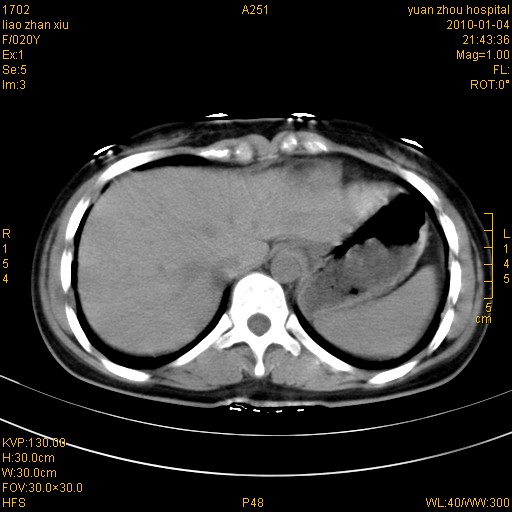

标题: CT23985:F20Y 外伤典型病例 [打印本页]

标题: CT23985:F20Y 外伤典型病例

左肾挫伤,包膜下积血。

左肾挫裂伤伴肾被膜下积血!另:肾周筋膜增厚!

1)左肾包膜下血肿。2)左侧肾挫伤可能;建议:行ct增强扫描检查。3)腰椎左侧横突骨折。

左肾挫伤,包膜下积血,l3、4左侧横突多发骨折。

双侧肾胞膜下出血,左侧较多。l3、4左侧横突多发骨折。

1、左肾挫伤,包膜下积血;

2、l3、4左侧横突多发骨折;

3、腹腔积气,考虑肠管破裂?

左肾挫伤,包膜下积血,L1、2、3、4左侧横突多发骨折。